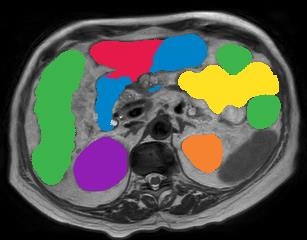

Vision transformers, with their ability to more efficiently model long-range context, have demonstrated impressive accuracy gains in several computer vision and medical image analysis tasks including segmentation. However, such methods need large labeled datasets for training, which is hard to obtain for medical image analysis. Self-supervised learning (SSL) has demonstrated success in medical image segmentation using convolutional networks. In this work, we developed a \underline{s}elf-distillation learning with \underline{m}asked \underline{i}mage modeling method to perform SSL for vision \underline{t}ransformers (SMIT) applied to 3D multi-organ segmentation from CT and MRI. Our contribution is a dense pixel-wise regression within masked patches called masked image prediction, which we combined with masked patch token distillation as pretext task to pre-train vision transformers. We show our approach is more accurate and requires fewer fine tuning datasets than other pretext tasks. Unlike prior medical image methods, which typically used image sets arising from disease sites and imaging modalities corresponding to the target tasks, we used 3,643 CT scans (602,708 images) arising from head and neck, lung, and kidney cancers as well as COVID-19 for pre-training and applied it to abdominal organs segmentation from MRI pancreatic cancer patients as well as publicly available 13 different abdominal organs segmentation from CT. Our method showed clear accuracy improvement (average DSC of 0.875 from MRI and 0.878 from CT) with reduced requirement for fine-tuning datasets over commonly used pretext tasks. Extensive comparisons against multiple current SSL methods were done. Code will be made available upon acceptance for publication.